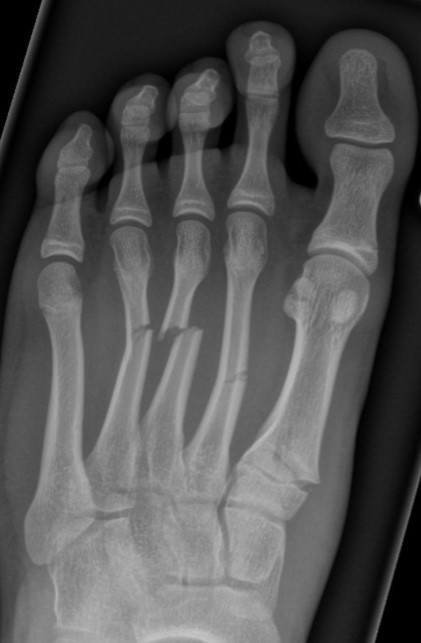

Case 1 - Pedestrian hit by car

Figure 1: Multiple metatarsal fractures